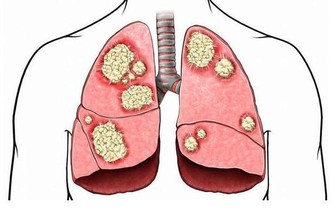

消化道出血或惡性腫瘤:消化道出血時,血液在患者的腸道中聚集。胃酸及腸道細菌將血液分解後,排出的屁有腥臭味。患腸道惡性腫瘤時,癌組織糜爛、出血,再加上細菌的分解發酵作用,也會使放出的屁有腥臭味。

若屁奇臭難聞,可能有消化道出血、菌痢、阿米巴痢疾、潰瘍性結腸炎、出血性小腸炎等炎症。此外,惡性腫瘤晚期,因癌腫組織糜爛,蛋白質腐敗,由於細菌的作用,放出的屁也會很臭。愛放屁且經常放臭屁的人就有可能患上大腸疾病,這時你就需要前去診斷了。

如果消化道出血時, 血液在腸腔內滯積, 或腸道發生炎症、潰瘍時, 排出的氣體往往比較腥臭,最好找醫生進行診治,這可能是罹患胃腸道腫瘤的警訊。當患有腸道惡性腫瘤時, 由於癌腫組織糜爛,, 蛋白質腐敗, 經肛門排出的氣體也可出現腐肉樣奇臭。